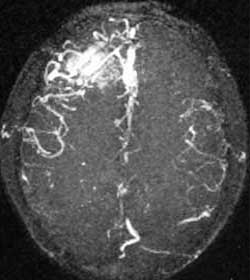

二、脑动静脉畸形(AVM)

---- Spetzler对AVM的分级方法已越来越多地被人们接纳和采用。脑AVM最危险的症状之一是出血。AVM每年的出血率为 3%~4%,第一年内再出血约6%。每次出血的致残率为30%,病死率为12.5%,而积极治疗的总残废率加病死率在10%以下。

---- 血管内栓塞对于单支或少数供血动脉的AVM,特别是新近出血的病例,可以达到微侵袭、痛苦小、疗效迅速的目的。 近来改变栓塞方式,将导管直接放置 畸形血管团内,注射NBCA胶,可使畸形团的解剖 治愈率提高至27%。再加上更细、超 滑的微导管问世,栓塞的并发症更为降低。针对大型、功能区 的AVM栓 塞可缩小其体积,改善血液动力学分布,以利于显 微外科技术切除或放射外科治疗,是后二者的重要辅助手段。

----立体定向放疗(γ-刀、χ-刀)对AVM是一种有希望的选择性治疗方法。据文献报道,AVM治疗后年消失率30%~50%,2年 消失率70%~90%,其消失速度与所用的照射量成正比,与AVM 的大小成反比。从治疗到AVM完全闭合之前每年的出血率 3%~4%,与自然出血史相同,所以对有出血史的患者,应优先采用栓塞或手术方法。大型AVM经若干次栓塞后体积缩小即可 放射治疗。但栓塞物质应是NBCA。其它颗粒或丝线栓塞,均有复发之虞。栓塞加立体定向放疗可使60%~80%的患者免于开颅 手术而获治愈。